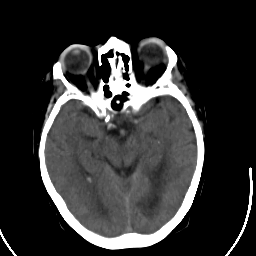

Stroke CT #2 -- Slice #10

[Home][Help][Clinical] Slice 10